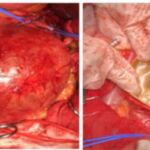

Ανεύρυσμα κοιλιακής αορτής-Ανοιχτή Αποκατάσταση

Η ανοιχτή αποκατάσταση ανευρύσματος κοιλιακής αορτής είναι χειρουργική επέμβαση κατά την οποία το παθολογικά διατεταμένο τμήμα της αορτής αντικαθίσταται με συνθετικό αγγειακό μόσχευμα για την αποκατάσταση της φυσιολογικής ροής του αίματος.